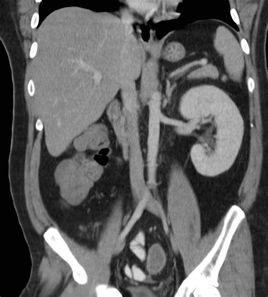

【CT表現】

腎缺如,CT顯示一側腎窩內腎影缺如,為周圍組織所充填。同側腎上腺也顯示相應缺如。對側腎可代償性肥大,或鏇轉不良和異位。額外腎,能滿意地顯示同一側相互分離的腎和輸尿管,對側腎臟同時存在。增強CT掃描可見一側腎完全未發育,僅有殘跡或一側腎小,但有功能。